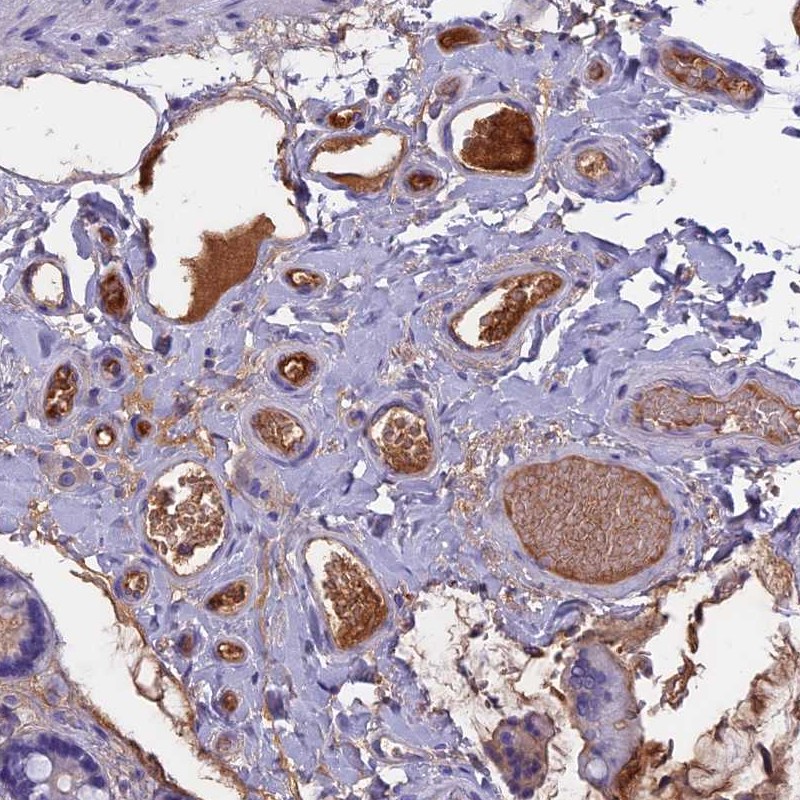

Immunohistochemical staining of plasma in human small intestine.